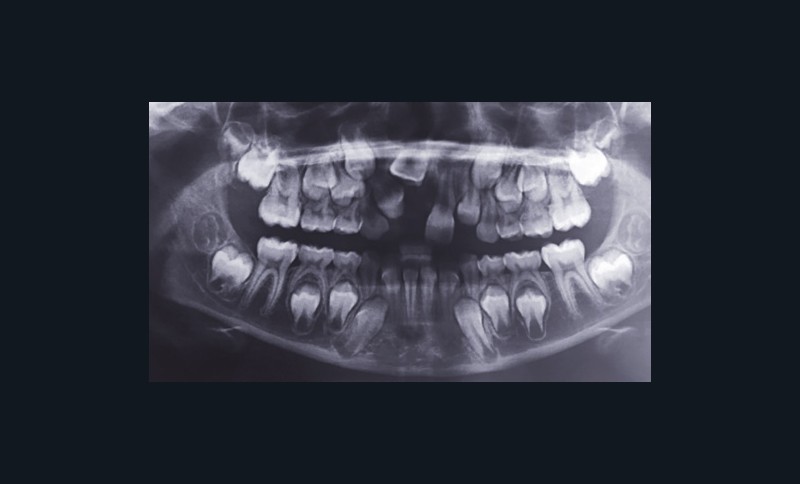

Une dent en rétention est une « dent immature non présente sur l’arcade, à l’âge où elle aurait dû faire son éruption ». Sans traitement, elle peut, en devenant mature, devenir enclavée ou incluse (fig. 1).